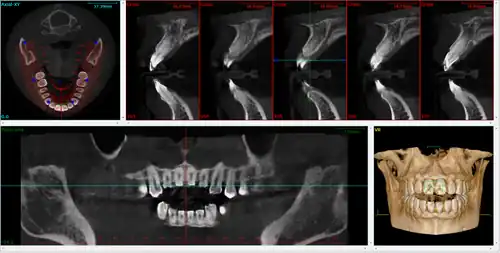

A dental cone beam scan offers useful information when it comes to the assessment and planning of surgical implants. The American Academy of Oral and Maxillofacial Radiology (AAOMR) suggests cone-beam CT as the preferred method for presurgical assessment of dental implant sites.[20]

Orthodontics

As a 3D rendition, CBCT offers an undistorted view of the dentition that can be used to accurately visualize both erupted and non-erupted teeth, tooth root orientation and anomalous structures, that conventional 2D radiography cannot.[21]